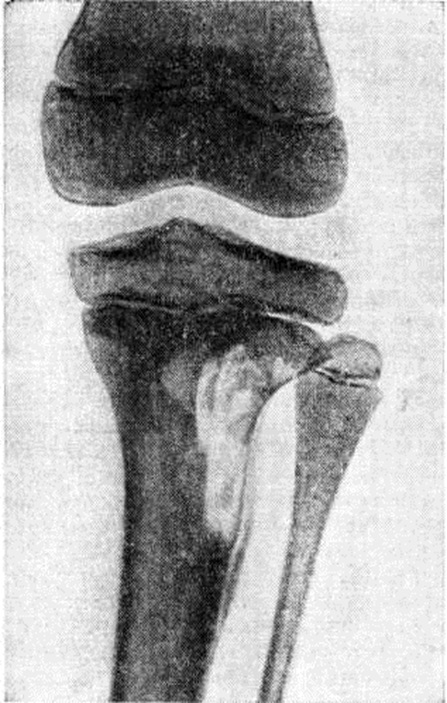

Рис. 3.

Рентгенограмма голени при болезни Хенда—Шюллера —Крисчена: обширный участок деструкции в метадиафизе большеберцовой кости.

У взрослых рентгенологическое проявления несколько отличаются. Чаще поражаются длинные трубчатые кости, в которых развиваются обширные периостозы (смотри полный свод знаний: Рахит). Деструктивные процессы в костях конечностей (рисунок 3) могут быть причиной их патологический переломов. Изменения в лёгких характеризуются чаще двусторонними мелкоочаговыми тенями, а иногда и гиперплазией внутригрудных лимфатических, узлов.